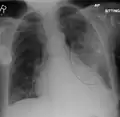

Left upper lobe pneumonia with a small pleural effusion.